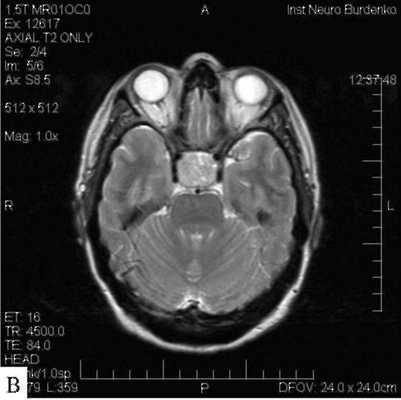

МРТ гипофиза с контрастом и без: А- гипофиз нормальных размеров (обведено кругом), В - симметричные кальцификации (стрелки)

МРТ гипофиза (обведено) без контраста и с с контрастом. В норме гипофиз равномерно накапливает контрастное вещество — становится светлым.

МРТ гипофиза с контрастом. После введения контрастного вещества в гипофизе происходит его накопления и он выглядит светлым. Только участок опухоли не накапливает контрастное вещество и выглятит темным (стрелка).